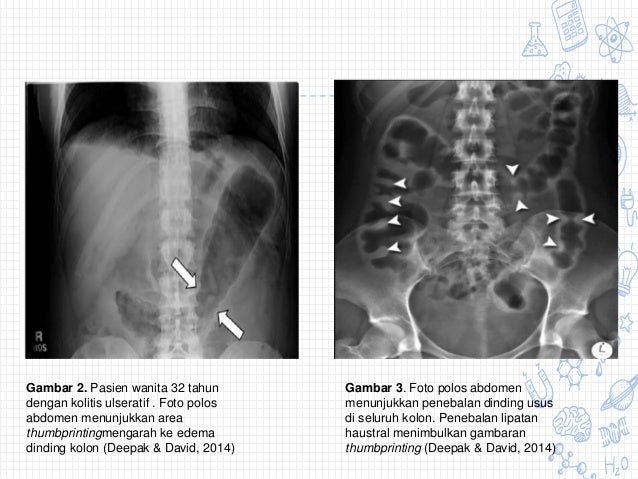

Laporan kasus kolitis , Sumber : www.slideshare.net

Barium enema , Sumber : www.slideshare.net